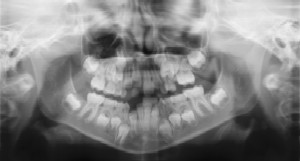

Radiographs (X-Rays) are a vital and necessary part of your child’s dental diagnostic process. Without them, certain dental conditions can and will be missed.

Radiographs detect much more than cavities. For example, radiographs may be needed to survey erupting teeth, diagnose bone diseases, evaluate the results of an injury, or plan orthodontic treatment. Radiographs allow dentists to diagnose and treat health conditions that cannot be detected during a clinical examination. If dental problems are found and treated early, dental care is more comfortable for your child and more affordable for you.

The American Academy of Pediatric Dentistry recommends radiographs and examinations every six months for children with a high risk of tooth decay. On average, most pediatric dentists request radiographs approximately once a year. Approximately every 3 years, it is a good idea to obtain a complete set of radiographs, either a panoramic and bitewings or periapicals and bitewings.

Pediatric dentists are particularly careful to minimize the exposure of their patients to radiation. With contemporary safeguards, the amount of radiation received in a dental X-ray examination is extremely small. The risk is negligible. In fact, the dental radiographs represent a far smaller risk than an undetected and untreated dental problem. Lead body aprons and shields will protect your child. Today’s equipment filters out unnecessary x-rays and restricts the x-ray beam to the area of interest. High-speed film and proper shielding assure that your child receives a minimal amount of radiation exposure.